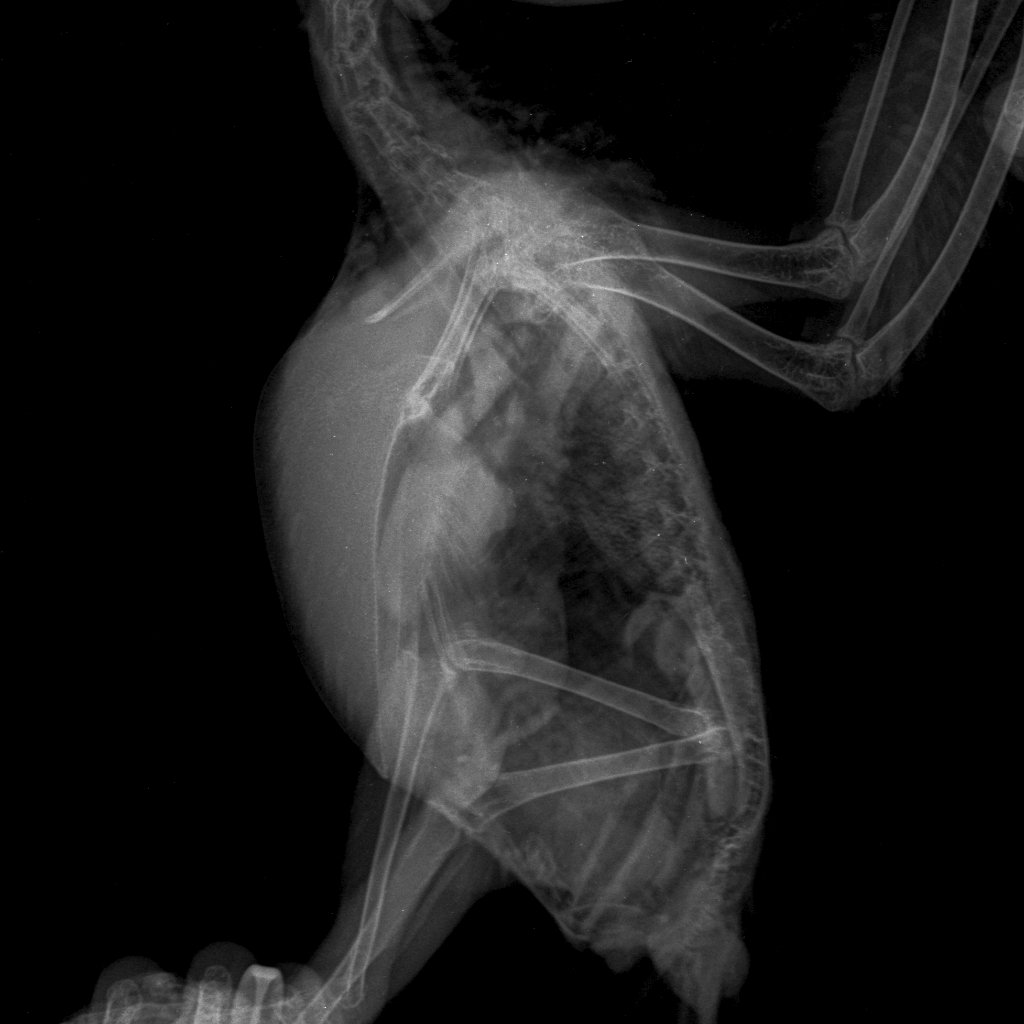

Были сегодня на приеме у врача, сделали рентген:

49550a8a-2ec7-45ef-8914-1df94ac3bfa06b384ea5-5e84-.thumb.JPE.5448ea1ec7752c165ad0122079b746cd.JPE

2137588860_6b384ea5-5e84-45ca-a26c-f60a48094715.thumb.JPE.ccd4e1350c9e68daa59d373cad1bbae2.JPE

Поставлен предварительный диагноз:

Аеросакулит.

Лечение:

Гептрал 1/8 таблетки 1 раз в день 30 дней.

Мелоксивет 0.3 мл 2 раза в день курс 14 дней.

Бифидумбактерин по 1/8 таблетки курс 14 дней.

Обработка от паразитов Стронгхолд.

Обработка клетки раствором Лайна.